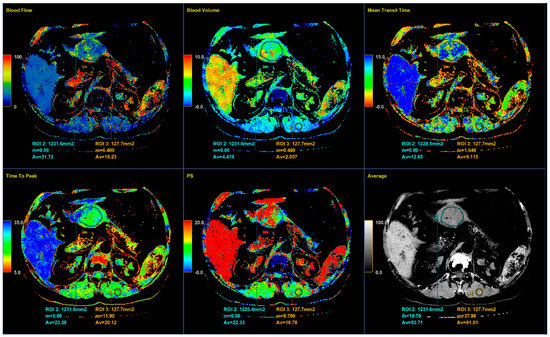

Perfusion CT data were analyzed by calculating perfusion according to the deconvolution method. The arterial input function was obtained from a 4–6 mm² circular region of interest (ROI) that was placed in the abdominal aorta. The arterial time-attenuation curve was derived automatically, and parametric colored maps were displayed for each of the four consecutive series of perfusion CT (Figure 4a). One radiologist placed a circular ROI as large as possible within the solid tumor region as well as in the nearby paravertebral skeletal muscles, taking care to avoid large vessels, at the reference and parametric images on each of the four consecutive slices (Figure 4b).

Color parametric maps of the following quantitative perfusion parameters have been automatically computed within these ROIs using the commercial software (Body Perfusion 4.0, GE Health-Care Technologies, USA): blood flow—BF (mL/min/100 g tissue); blood volume—BV (mL/100 g tissue); mean transit time—MTT (s); permeability surface area product—PS (mL/min/100 g tissue); and time to peak—TTP (s) (Figure 5). The values of the perfusion parameters of tumor were recorded for each section of gastric tumor ROI, and the same was done for muscle ROIs. Mean values of the perfusion parameters derived from the four consecutive sections were averaged and used for further analysis.

Figure 5. Color parametric maps of the same tumor and muscle ROI (area in square millimeters) automatically computed by the commercial deconvolution-based CT perfusion software. Axial CT sections show the average values of perfusion parameters BF, BV, MTT, TTP, PS, and average density measured for tumor and muscle.